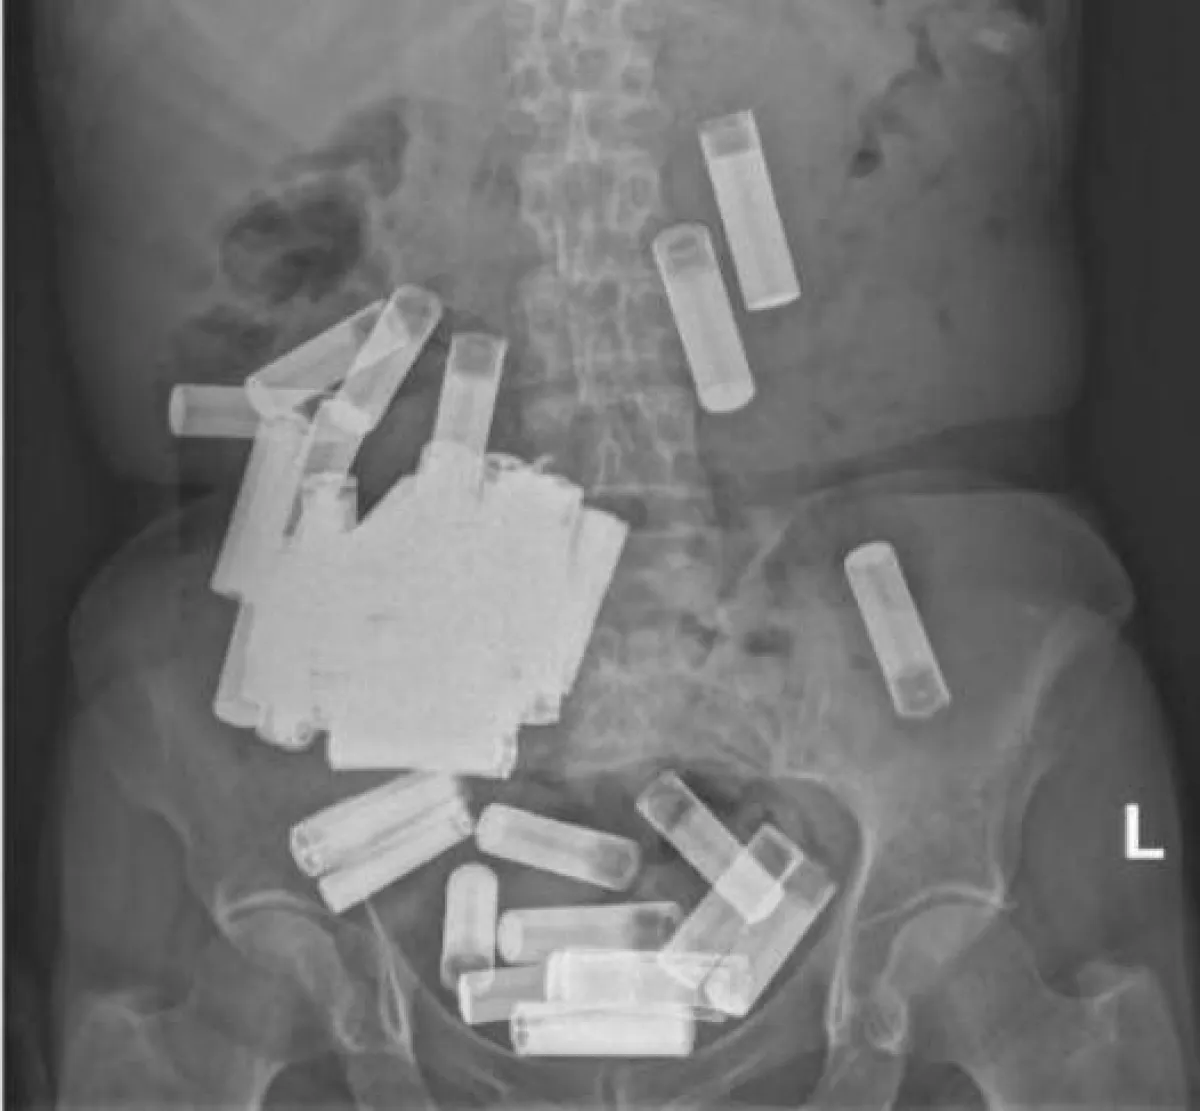

سونار يكشف البطاريات داخل معدة السيدة - الصورة من موقع irishexaminer.com

أظهرت الأشعة السينية التي تم إجراؤها بعد العرض التقديمي للمريضة في قسم الطوارئ بالمستشفى وجود أجسام غريبة في جسدها. بأعجوبة ، لم يكن أي منها يعيق جهازها الهضمي، وظهر أنها "بطاريات متعددة" موجودة في جميع أنحاء بطنها ، ولم يُعرف سبب تناولها لهذا العدد الضخم من البطاريات.

ووفقًا لتقرير الحالة الذي نُشر فالسيدة كانت قد أخرجت خمس بطاريات AA بعد فترة وجيزة من دخولها المستشفى، مما رفع العدد الإجمالي الذي تم تناولته في فعل واضح لإيذاء النفس المتعمد إلى 55 - وهو ما يعتقد الأطباء أنه رقم قياسي.